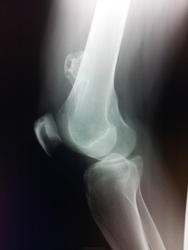

Костно-хрящевой экзостоз ("базис"-костный, "надстройка"-хрящевая.Только почему эта "политическая система" болит не понятно? Может быть не будет лишней консультация онколога?).

Костно-хрящевой экзостоз, она же остеохондрома. Обычно боли возникают при сдавлении окружающих мягких тканей, сосудисто-нервного пучка, при переломе основания остеохондромы и при ее озлокачествлении. Рейнберг описал бурсит костно-хрящевого экзостоза, который тоже может вызывать боль.

Некрасивая "надстройка"-то. Архива за "сознательную" жизнь нет, конечно.)))

Консультация онколога не помешает однозначно, т.к. экзостозы могут озлокачествляться!